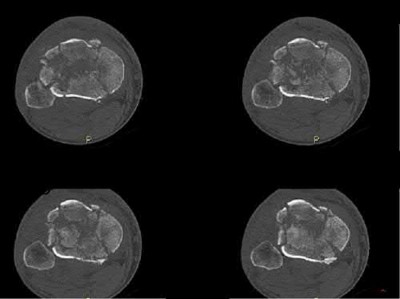

Question 13

A patient presents to the emergency department with acute knee swelling following a high-energy trauma. T1-weighted MRI is obtained and shown. The distinct layering effect seen in the suprapatellar pouch is most strongly associated with which of the following underlying injuries?

Explanation

Correct Answer: Intra-articular fracture

The MRI scan demonstrates a lipohemarthrosis, characterized by the layering of fat, serum, and red blood cells in the joint space. The superior layer contains fat (high signal intensity on T1), the middle layer contains serum, and the dependent layer contains red blood cells. The presence of a lipohemarthrosis is highly indicative of an intra-articular fracture, which allows marrow fat to escape into the joint cavity. While ligamentous and meniscal injuries can cause a hemarthrosis, they do not typically introduce marrow fat into the joint unless accompanied by an osteochondral defect or fracture.

Question 24

A patient presents with acute knee swelling following trauma. MRI scans (T1 and T2-weighted) are shown. The layering effect seen within the joint space is most strongly associated with which of the following underlying injuries?

The MRI shows lipohemarthrosis, characterized by layering of fat (superior, high signal on T1), serum (central, low signal), and red blood cells (inferior, low signal). This finding is highly indicative of an intra-articular fracture, which allows marrow fat to escape into the joint space.

Question 34

A patient presents with acute knee swelling following trauma. T1- and T2-weighted MRI scans are shown, demonstrating a characteristic layering effect within the joint effusion. This finding is most strongly associated with which of the following underlying injuries?

Correct Answer: C

The MRI scans demonstrate a lipohemarthrosis, characterized by the layering of fat (superiorly, high signal on T1), serum (centrally), and red blood cells (inferiorly, low signal). The most common cause of a lipohemarthrosis is an intra-articular fracture, which allows marrow fat to escape into the joint space. While an ACL tear can cause a hemarthrosis, it typically does not produce a lipohemarthrosis unless accompanied by an osteochondral fracture.

Question 42

A 35-year-old skier sustains a twisting injury to the knee. An MRI is obtained, and a T1-weighted sagittal image is shown. The layering effect seen in the suprapatellar pouch is most strongly associated with which of the following underlying injuries?

The MRI demonstrates lipohemarthrosis, characterized by a distinct layering effect in the suprapatellar pouch. Fat (which has high signal intensity on T1-weighted images) layers superiorly, serum layers centrally, and red blood cells layer inferiorly. This finding is highly indicative of an intra-articular fracture, which allows marrow fat to escape into the joint space.